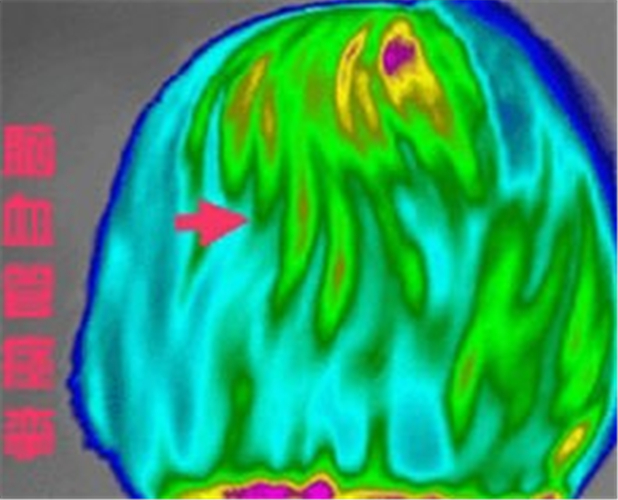

診斷監測腦血管痙攣